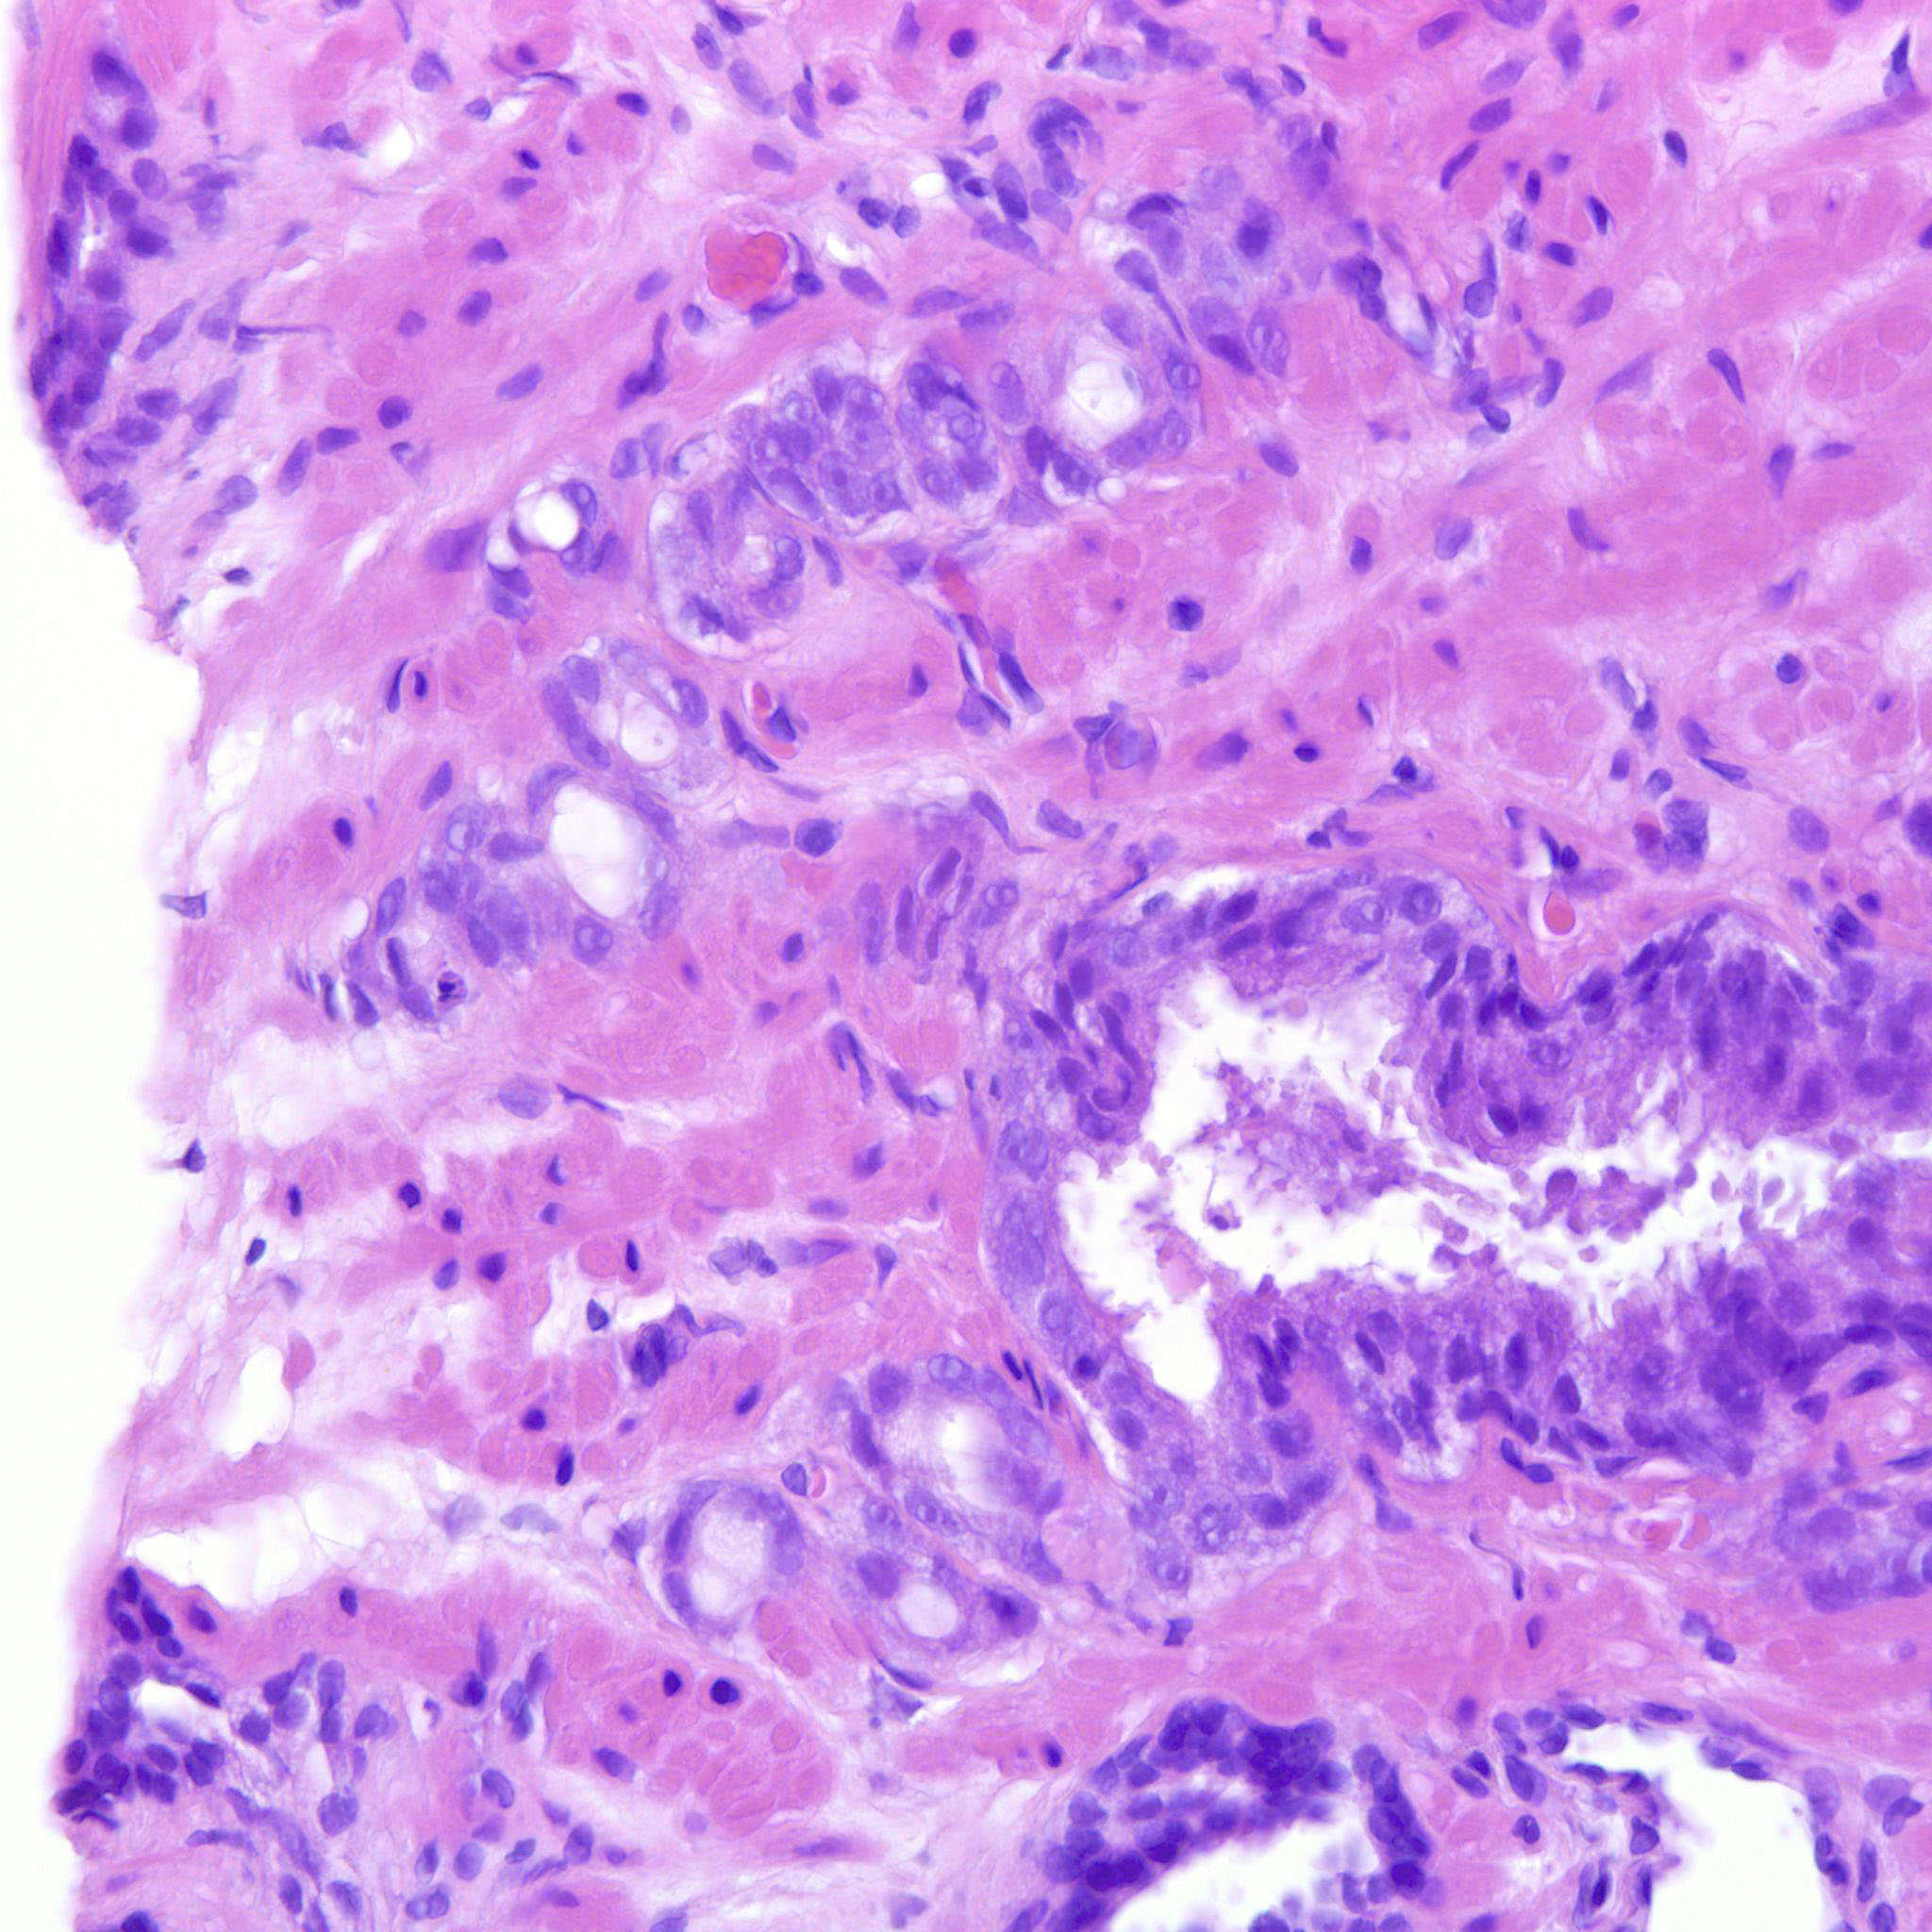

Prostate cancer grading

Case ID: 685